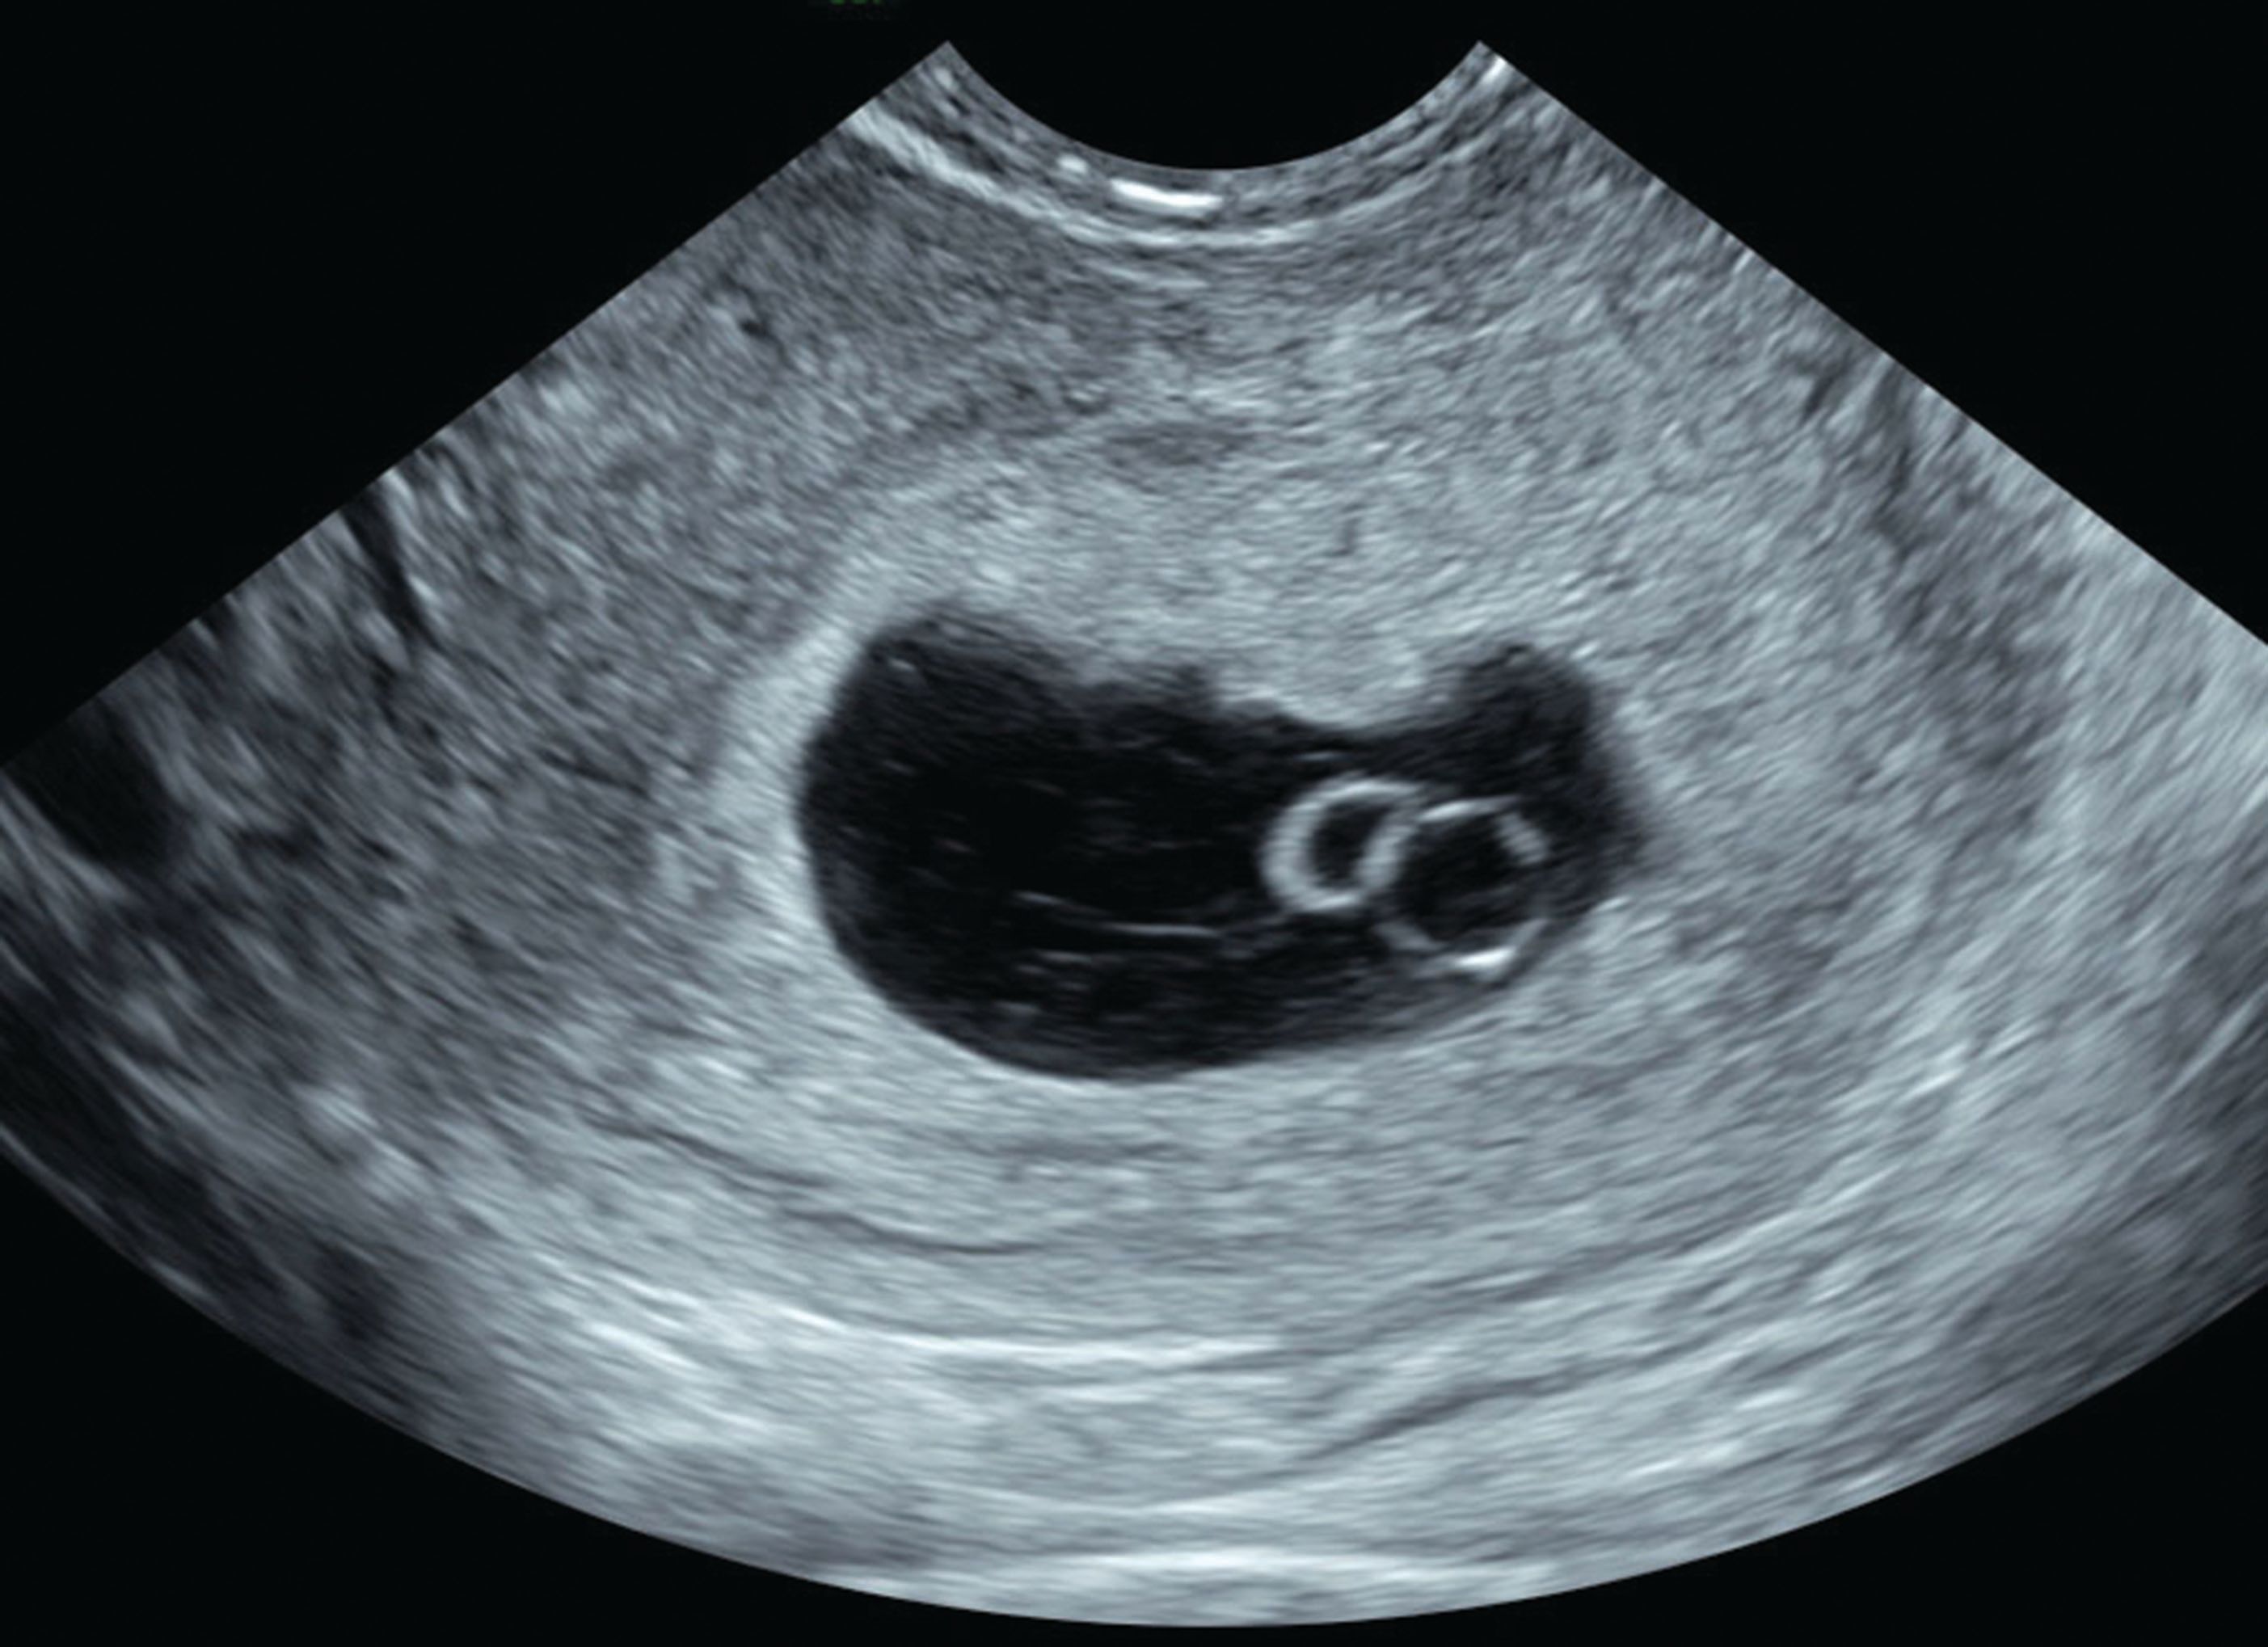

Answers to common questions related to an ultrasound examIf an ultrasound is done at 6 to 7 weeks and a heartbeat is not detected does that mean there is a problem. Is it normal not to see baby on ultrasound 6 weeks. A yolk sac can be seen at 5 12 weeks and fetal pole small embryo seen at approximately 6 weeks.

In almost all cases miscarriage diagnosis at 6 weeks is hard to make and you will likely be asked to have another scan in a one or two weeks time. When youre 60 weeks pregnant your babys hearts should be beating. A twin ultrasound at 6 weeks needs to be done vaginally to detect twins this early in your pregnancy.

The pregnancy is a miscarriage. At 6 weeks you wont in general be able to see much detail of your baby. In addition if an earlier ultrasound revealed a fetal heartbeat and a subsequent ultrasound finds no heartbeat this also indicates a miscarriage.

Your doctor wants to know if its high in. Often seeing no yolk sac or a yolk sac that is smaller than normal or otherwise misshapen at 6 weeks can be a sign of miscarriage. Risk of Miscarriage according to Fetal Heart Rate.

Be aware though that sometimes 6 weeks is too early to tell. Seeing no baby on the. Often seeing no yolk sac or a yolk sac that is smaller than normal or otherwise misshapen at 6 weeks can be a sign of miscarriage.

That is not all of the gestational sac comes way. What week does fetal pole appear. Often seeing no yolk sac or a yolk sac that is smaller than normal or otherwise misshapen at 6 weeks can be a sign of miscarriage.

How long does a 6 week miscarriage last. A vaginal sonogram at 6 weeks and 4 days can usually see a heartbeat. The fetal pole is usually identified at 65 weeks with transabdominal ultrasound.

An abdominal ultrasound can detect a heartbeat at 6 to 8 weeks time. Falling levels of hCG human. Ultrasound scans can detect a fetal heartbeat at approximately 6-7.